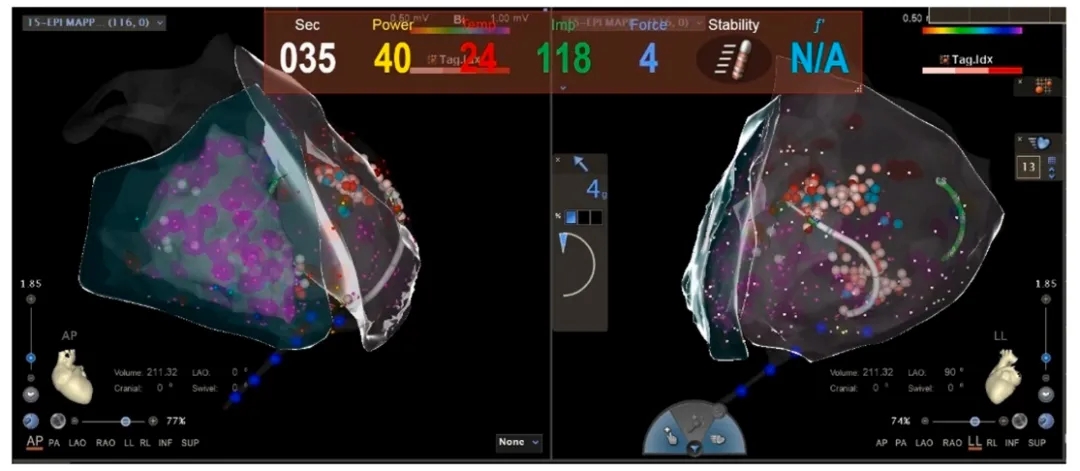

AF导管消融进行了40分钟,经过双侧肺静脉电隔离联合左心房顶部线消融治疗,成功恢复了窦性心律。其中环肺静脉隔离,并在其基础上辅以线性消融及复杂碎裂电位消融综合治疗以确保疗效(图3)。

图3:左心房CARTO标测图中的消融部位